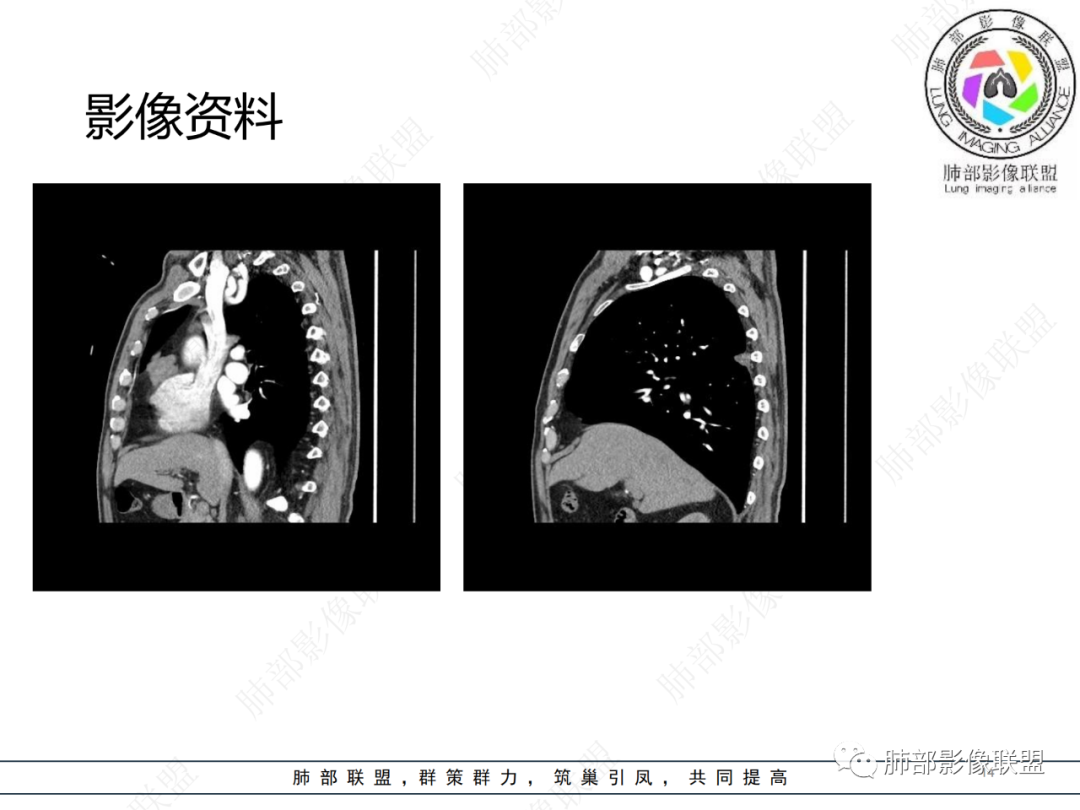

老年男性,体检发现纵隔占位,胸部CT检查所见,前纵隔多发软组织结节或肿块,右侧胸膜结节,密度均匀,边缘分叶,未见明显坏死,强化尚明显均匀强化,冠状位第1张图,左侧膈肌连续性中断,未见明确脾脏显示,可以考虑转移?异位组织(异位脾脏)?如果左侧膈肌确实断裂且无脾脏那么考虑异位脾脏可能大,或者代偿的淋巴结,再有鉴别神经源性肿瘤,入鞘瘤,不过鞘瘤一般会有ab区,这个病例没有。

前纵隔结节及右肺下叶背段胸膜下结节,增强扫描明显强化,所示图像未见脾脏,考虑异位脾并神经源性肿瘤或孤立性纤维瘤,鉴别胸腺瘤并神经源性肿瘤或孤立性纤维瘤。

右前纵膈不规则软组织密度影,密度均匀,分叶,中度强化,心包受侵,右侧胸膜不规则结节,明显强化,考虑胸腺瘤B2或B3型伴胸膜转移,鉴别胸腺癌